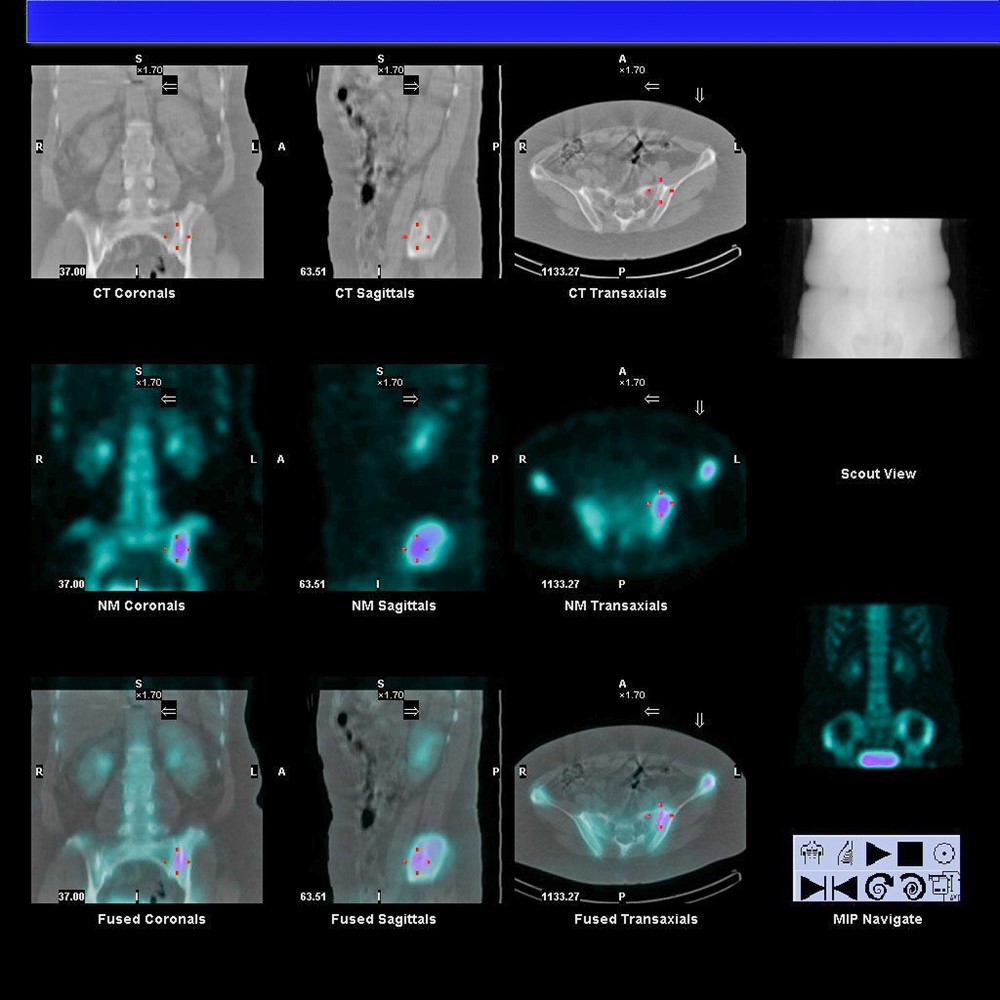

所以,黃伯仁醫師為婦人施行薦髂關節注射與神經燒灼手術,發現可以暫時性改善病情,於是再利用核子醫學影像檢查證實存在「薦髂關節病變」,實行「薦髂關節骨釘固定手術」後,讓盧女士如獲重生。

黃伯仁醫師利用核子醫學影像檢查證實病人下背痛原因是「薦髂關節病變」。